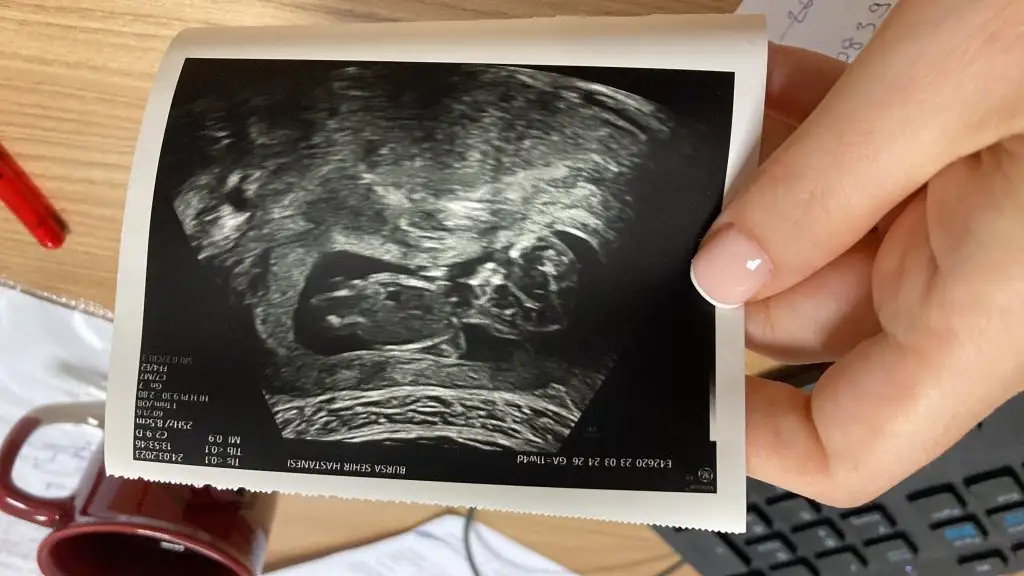

Banada bakarmısınız rica etsemHayırlı olsun

Merhaba banada tahmin yapar misinizKız bu

Erkek işte besbelliKızlar bizim cinsiyetimizi de söyler misiniz ? Elimde sadece bu foto var

Net olmamakla birlikte erkek gibiiBanada bakarmısınız rica etsem